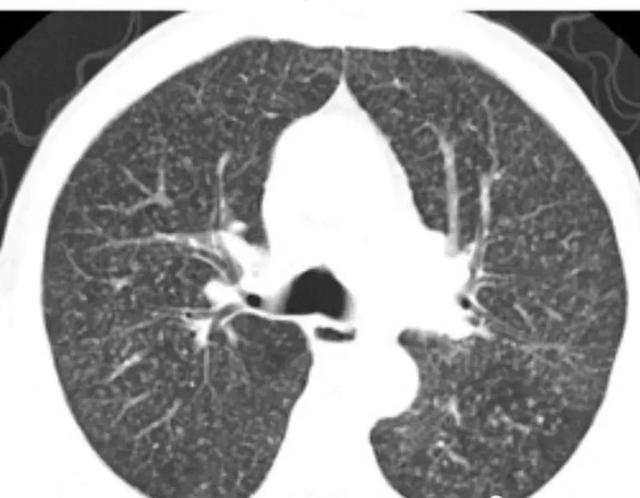

【影像学表现】

(1)X线:初期仅见肺纹理增多,约在两周才出现典型粟粒样结节。表现为广泛均匀分布于两肺的粟粒大小的结节状密度增高影。其特点为病灶分布均匀、大小均匀和密度均匀,即所谓“三均匀”表现。由于病灶数量多且分布密集,两肺野可呈磨玻璃样改变。分布密集的粟粒样结核可将肺纹理遮盖,使正常的肺纹理不易辨认。大小一致的粟粒样致密影,其直径1~2mm。境界较清楚,若为渗出性病灶则其边缘不清。晚期粟粒状密度增高影常有融合的倾向。

(2)CT:易显示粟粒结节,尤其HRCT 可清晰显示弥漫分布的粟粒性病灶,更加典型地显示粟粒结节分布均匀、大小均匀和密度均匀的“三均匀”的特点。

肺结核的分型诊断标准,肺结核的分型及影像学表现

急性粟粒型肺结核 CT肺窗,两肺可见分布均匀、大小均匀、密度均匀的粟粒状影,边界清晰